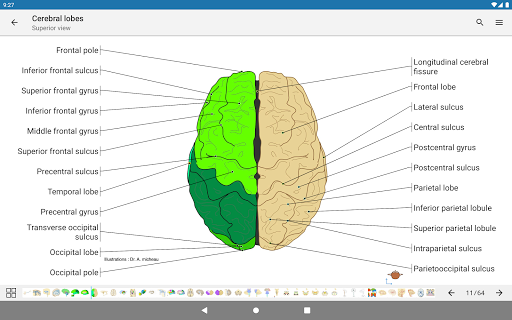

* اعثر على الأجزاء التشريحية الخاصة بك بسهولة أكبر بفضل ميزة البحث الجديدة والأكثر سهولة وقوة

* تحسين رؤية تعريفات الأجزاء التشريحية

* تصفح بين الأجزاء التشريحية باستخدام روابط الوصف